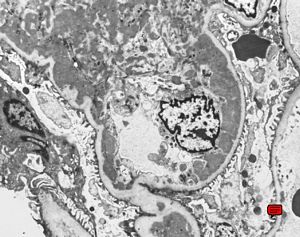

M,20y. | IgA nephropathy (Berger disease)

F,47y. | IgA nephropathy (Berger disease)

M,21y. | IgA nephropathy (Berger disease)